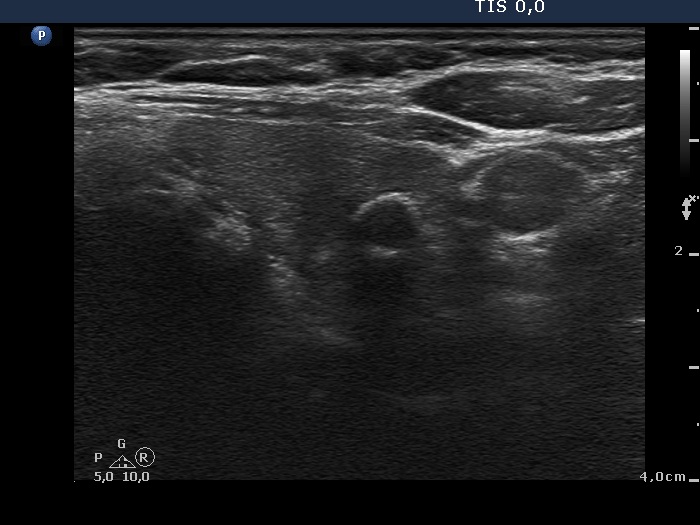

100 consecutive patients with thyroid nodule - Case 39. |

Clinical presentation: a 71-year-old woman was referred for evaluation of a slowly growing nodule known for more than 30 years. The patient had difficulties in swallowing.

Ultrasonography. The thyroid was hypoechogenic. A large lesion occupied the lower 2/3 of the left lobe and the isthmus. The lesion was composed of multiple hyperechogenic areas. There was another nodule in the upper part of the left thyroid. This smaller lesion presented coarse calcification.

A left lobectomy was performed. Histopathology disclosed benign hyperplastic nodules. There were no lymphocytic thyroiditis.

Comment. The non-nodular part of the thyroid was hypoechogenic. It would be almost diagnostic for autoimmune thyroiditis in a younger patient, however in elderly even such degree of hypoechogenicity may be a normal finding.